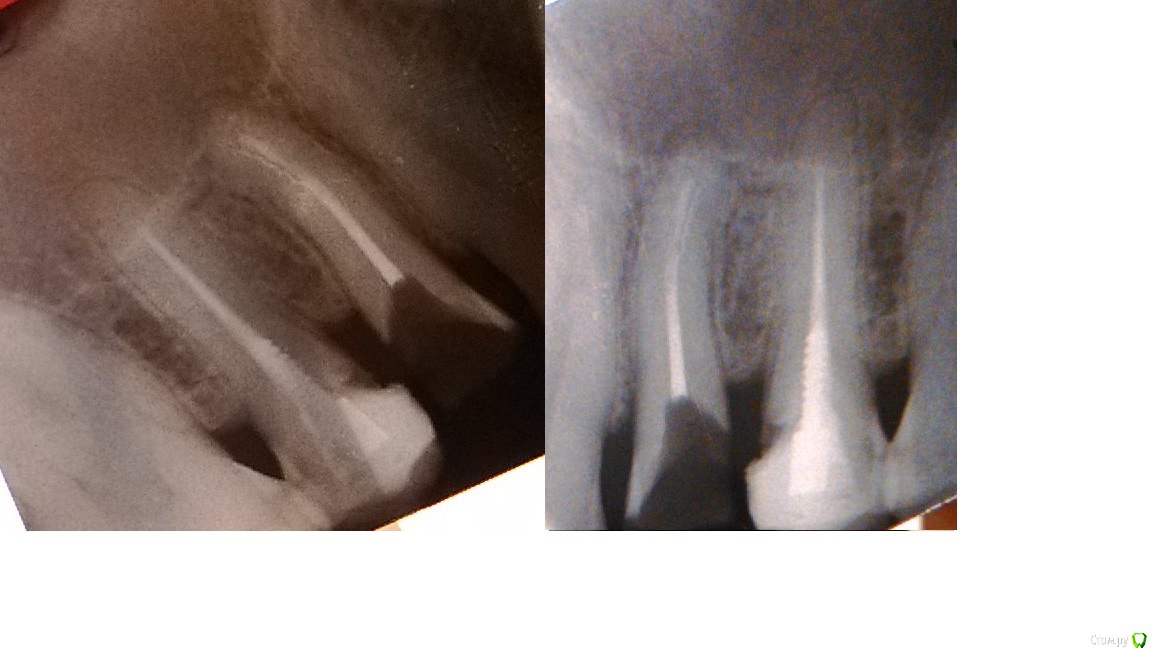

Максим-50 Опубликовано 23 марта, 2015 Автор Поделиться Опубликовано 23 марта, 2015 2. принципиально состояние костных тканей около верхушек обсуждаемых зубов3. если состояние тканей корня 4-и удовлетворительное возможно его востановление вкв и коронкой4. зуб 5 лечить вкв и коронкаПо поводу прогноза все зависит от многих факоторов( гигиены, сосояния полости рта в целом, качества плобировки каналов и качества констукции и т.д)Нужен хороший снимок! ( либо переделать, либо правильно сфотографировать имеющийся) про 4-ый врач, после того как начала лечить кариес, сказала: "на удивление зуб крепкий", после чего направила к ортопеду. Переснятый снимок: Ссылка на комментарий

krokomot Опубликовано 23 марта, 2015 Поделиться Опубликовано 23 марта, 2015 Вот снимки другое дело) Нужно перелечивание каналов в обоих зубах. В 4-ке получится скорее только у профессионального эндодонтиста с микроскопом ( без последствий), 5-й думаю вполне можно и без микроскопа, но перелечить обязательно, далее повторюсь если ткани, зуба в удовлетварительном состоянии все будет впорядке вкв +мк, при хорошей и регулярной индивидуальной гигиене и проф. гигиене сможете пользоваться думаю оч долго ( больше 10), Но все условия нужно соблюсти! Ссылка на комментарий

Максим-50 Опубликовано 24 марта, 2015 Автор Поделиться Опубликовано 24 марта, 2015 Понял вас. Значит Вот снимки другое дело) Нужно перелечивание каналов в обоих зубах. В 4-ке получится скорее только у профессионального эндодонтиста с микроскопом ( без последствий), 5-й думаю вполне можно и без микроскопа, но перелечить обязательно Понял вас. Значит буду обращаться в первую клинику, там где эндодонтию и предлагали (профессионалы и оборудование там есть). Ссылка на комментарий